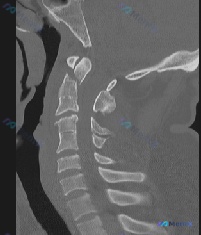

- 影像:张口颈椎X光片、矢状位CT、CT轴位血管造影

影像分析提示:

- 枢椎(C2)齿状突基底部骨折,骨折块与椎体分离

- 齿状突骨折块伴随寰椎向前移位,寰枢关节不稳/半脱位

- 寰枢复合体稳定性完全丧失,需警惕脊髓/延髓压迫风险